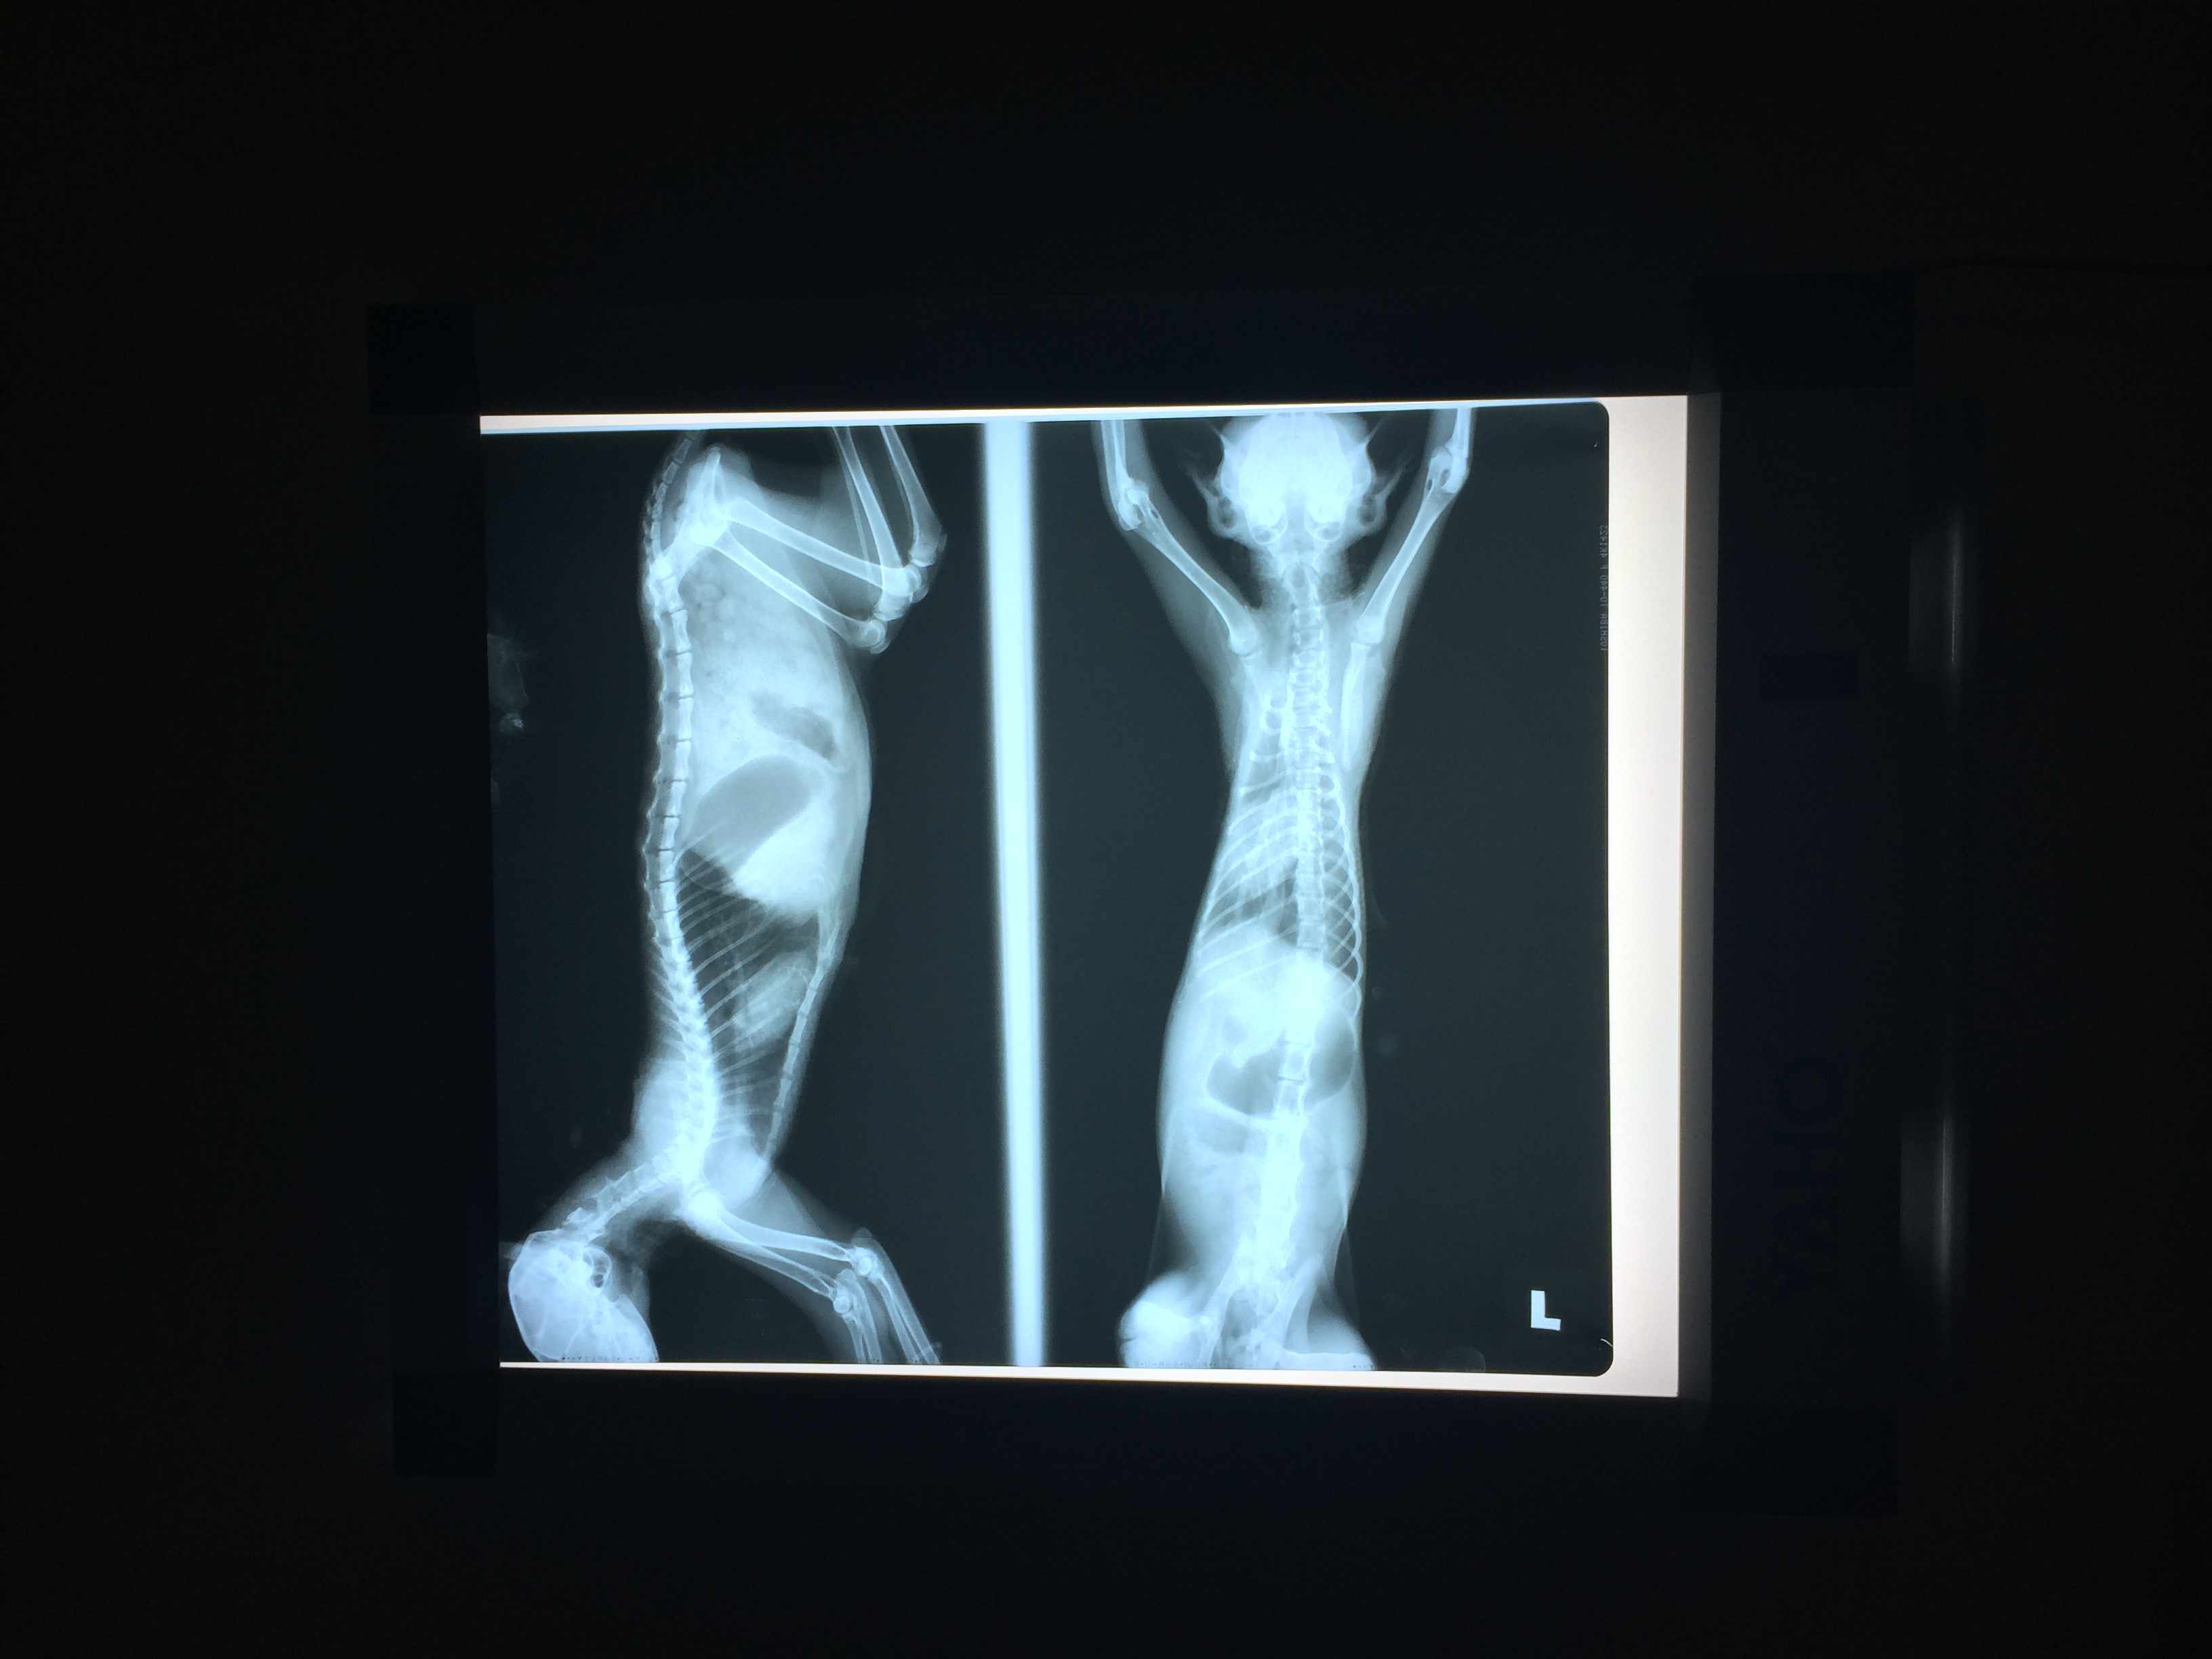

這次回去他狀況很差,肚子凹陷,食慾不佳,呼吸大又急促,想說檢查一下好送養,以為他只是營養不良,結果是胸腔赫尼亞,腸子佔胸腔1/2,呼吸窘迫,精神食慾不佳,貧血很嚴重,動手術才有存活機會。

12/16 醫生判定急需手術,開刀後發現除了腸子,整個肝臟都掉進胸腔,腸子有些發炎。